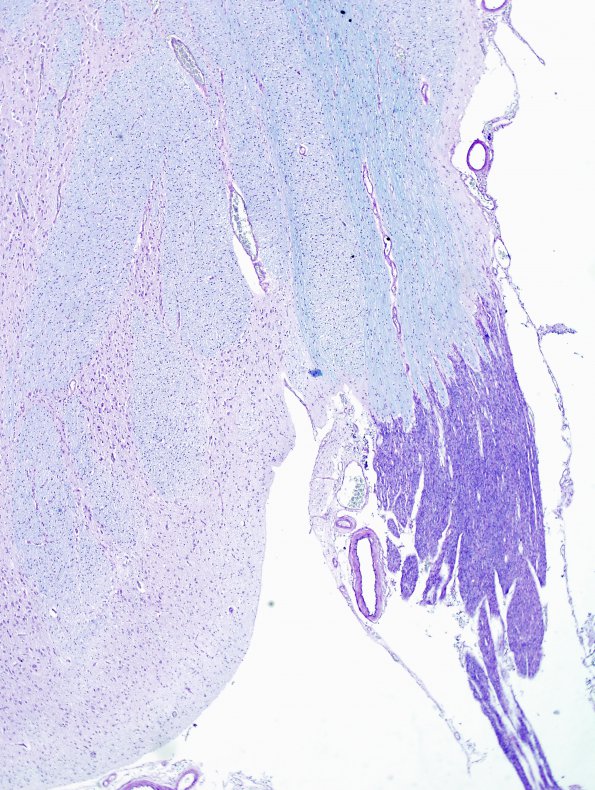

Washington University Experience | BASIC PROCESSES | CNS-PNS Junction | 2B2 Brainstem, neonate, V Nerve (Case 2) LFB-PAS 2A

Although the amount of central myelin is limited in this immature brain, there is a clear separation of central light blue green oligodendroglial myelin from the robustly stained purple PNS component. (LFB-PAS)